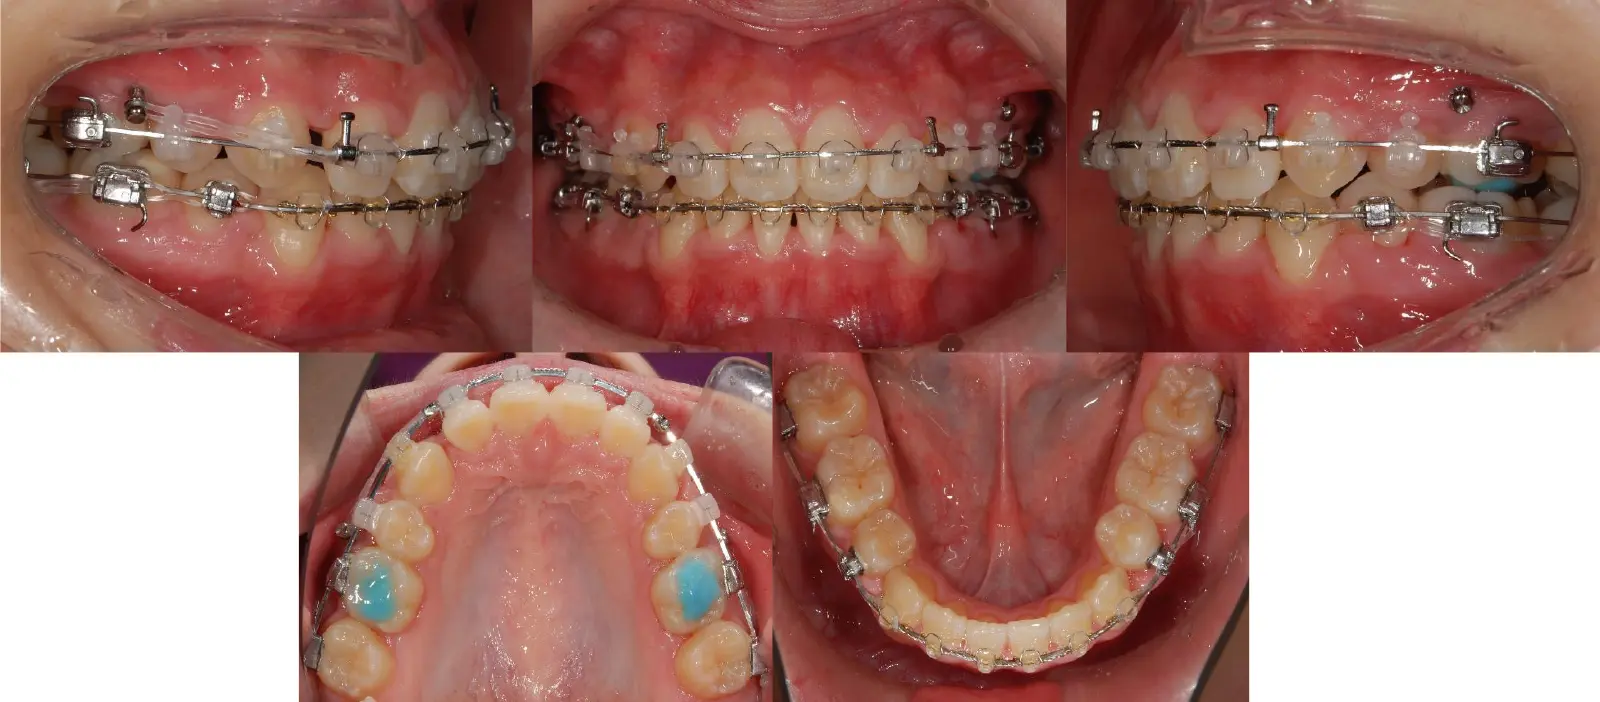

アングルⅡ級 開咬を伴う上顎前突症

- 主訴

前歯がかみ合わない

- 年齢

10代

- 治療期間

2年1ヶ月

- 治療回数

24回

- 治療に用いた主な装置

カスタムメイド型マルチブラケットタイプのデジタル矯正装置(インシグニア)

i-station(口蓋型アンカースクリュー)

- 治療費

650,000円(税別)、調整料5,000円(税別)

※伊那分院にて治療

- 抜歯部位

上顎第一小臼歯2本

下顎第二小臼歯2本